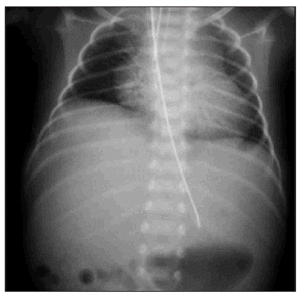

Se presenta el caso de un recién nacido mujer de 33 semanas de edad gestacional, hijo de madre primigesta, cuyo embarazo fue controlado sin incidencias reseñables salvo movimientos fetales discretamente disminuidos. El parto se desencadenó de manera espontánea, con registro cardiotocográfico normal, realizándose cesárea por no progresión. El recién nacido pesó 1.800 g y presentó depresión respiratoria grave inmediata con secreciones espesas precisando aspiración e intubación, con dificultad para establecer una ventilación y oxigenación adecuadas durante los primeros minutos de vida. El test de Apgar fue de 1/4/4, precisando adrenalina y bicarbonato. El pH de cordón fue 7,28/7,34. Desde su ingreso se apreció hipotonía generalizada grave con mínima actividad motora, depresión del nivel de conciencia sin respuesta al dolor, así como ausencia de respiración espontánea, precisando ventilación mecánica. Los reflejos osteotendinosos eran débiles, los reflejos primitivos estaban abolidos y presentaba afectación del tronco cerebral. Se realizó electroencefalograma donde se objetivó enlentecimiento de actividad cerebral de bajo voltaje compatible con encefalopatía difusa de grado moderado-grave a las 12 h de vida y ausencia de actividad eléctrica a las 60 h. No presentó convulsiones ni se observaron alteraciones en la ecografía cerebral realizada precozmente. Los rasgos fenotípicos fueron normales salvo leve hipotrofia muscular de miembros inferiores y turbidez corneal. En la radiografía de tórax (fig. 1) se apreció elevación del hemidiafragma derecho y costillas finas con posible hipoplasia pulmonar. Ante la sospecha de enfermedad neuromuscular se estudió a la madre que fue diagnosticada de distrofia miotónica de Steinert. No había otros antecedentes familiares de enfermedad neuromuscular. El recién nacido falleció a las 62 h con los diagnósticos de encefalopatía hipóxico-isquémica grave y probable DMC, realizándose biopsia muscular donde se observaron fascículos constituidos por fibras musculares de muy pequeño tamaño (7-14 micras) mostrando imágenes de centralización nuclear y miotubos, sugerentes de DMC.

Figura 1. Radiografia de tórax donde se observan hipoplasia pulmonar derecha y costillas finas.

Hemos expuesto un caso de DMC grave de diagnóstico posnatal sospechada por la intensidad de la depresión al nacimiento en ausencia de indicadores de pérdida de bienestar fetal, los hallazgos de la radiografía de tórax, así como el diagnóstico posterior de enfermedad materna. En nuestro caso la dificultad en establecer una ventilación adecuada en los primeros minutos de vida provocó el episodio asfíctico posnatal, origen de la encefalopatía hipóxico-isquémica grave. Aunque la forma de presentación más frecuente de DMC es aquella en la que se evidencian los signos clínicos clásicos de la enfermedad descritos previamente, éstos pueden pasar desapercibidos por una forma de presentación grave en la que la encefalopatía hipóxico-isquémica aparece como diagnóstico principal.